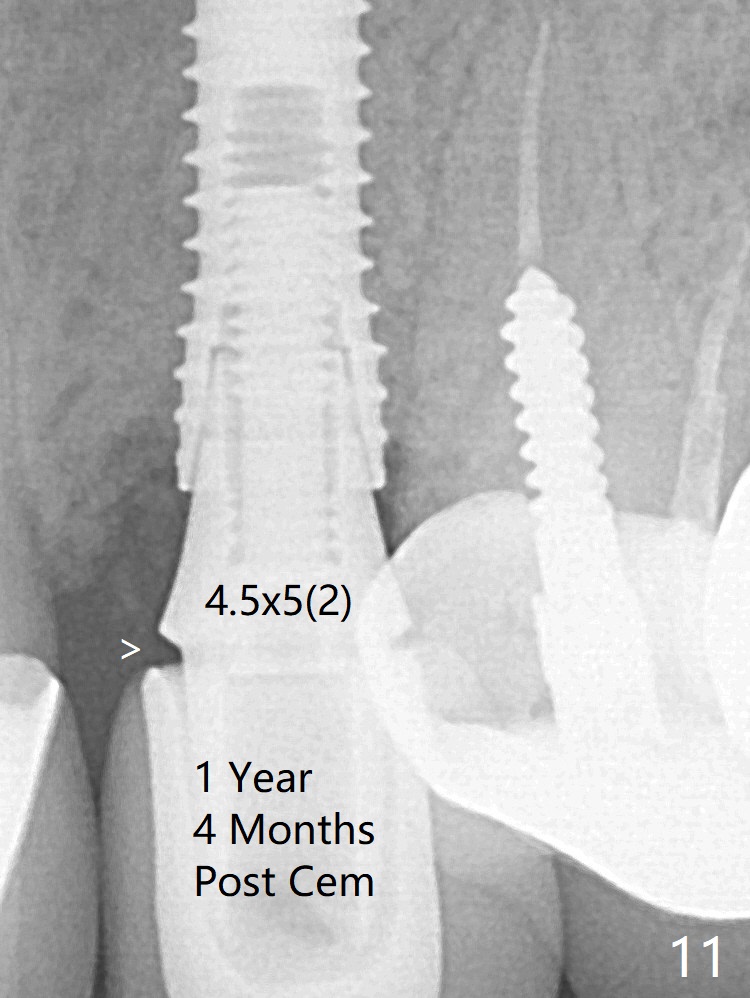

In spite of severe apical infection (Fig1,2 *), a thin narrow strip of the buccal plate (arrowheads, corresponding to the keratinized gingiva) is present when the tooth #11 is extracted. The thin bone keeps the bulging alveolus, i.e., reservoir for bone graft (Vanilla/Osteogen Fig.4 *) after placement of a 3.8x16 mm implant (Fig.3,4). A 4.5x1 mm temporary abutment, placed and trimmed for an immediate provisional, seems to be short in cuff. When an implant is placed deep to prevent periimplantitis, the cuff should be longer, i.e., 3 mm. X-ray should be taken for the depth confirmation after temporary abutment placement. Fig.3: a 2 mm drill in place, 18 mm in bone vs. 16 mm of implant placed ~ 2 mm subcrestal (Fig.4). A narrow implant (3.8 mm) is chosen over 4.5 mm because of the extensive buccal plate defect. While the hard tissue around the implant seems to be healthy 5 months postop (Fig.7), the soft tissue is not (Fig.8). Indeed PFM helps shade match in this case as well (Fig.9,10). Switching abutments (from temporary to cemented) makes it difficult to seat the crown. Post cementation X-ray leaves record for future contact loosening. The buccal gingiva remains erythematous associated with open margin (Fig.11 >) 1 year 4 months post cementation.